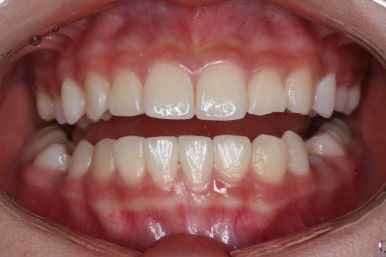

치료 종료 후의 모습입니다.

얼굴 모습의 큰 변화 없이 양호한 모습 그대로 마무리가 되었고, 웃을 대 위아래 치아의 중앙이 안맞았던 부분도 개선되었습니다.

치아가 잘 올라온 것을 볼 수 있습니다.